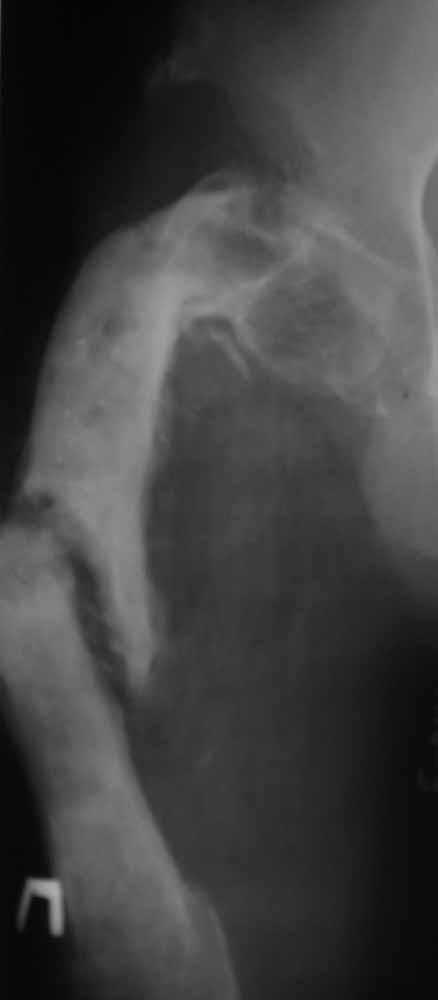

Пациент 29 лет. Неоднократно оперированная Coxa Vara.

В анамнезе этапные операции по поводу устранения Coxa Vara, формирование артродеза коленного сустава, удлинения бедра. В данный момент беспокоит укорочение 7 см, эквинус стопы. Объективно: - местный статус виден на фото, сосудистых и неврологических расстройств нет. Обратился в консультативном порядке, настроен на удлинение голени в г.Волгограде. (со слов больного - не берут без санации очага на голени). Ваши предложения? Из кулуарных соображений - а не актиномикоз ли это? Иссечение рубцов+ VAC+ Стержень с аппаратом + микрососудистый трансплантат(?)

Ваш вопрос, коллега, вполне правомерен. В советское время те из нас, кто занимался костно-гнойной инфекцией видели достаточное количество подобных несчастных, кочующих из стационара в стационар. Своеобразный госпитализм приводил к тому, что люди тратили всю свою, как правило достаточно короткую жизнь, на лечение зачастую реально неизлечимых процессов. В данном случае имеющаяся рентгенологическая картина груботрабекулярной перестройки кости, сочетающаяся с участками склероза говорит, скорее всего, о том, что вся имеющаяся картина, дополненная чудесными фотографиями,вполне укладывается в клинику гематогенного остеомиелита, которым и страдает пациент с детства. Никакие санации, к сожалению, не приведут в данном случае к излечению, так как все имеющиеся рубцы являются зоной жизни этой самой инфекции. При продолжении лечения не исключено достаточно раннее развитие амилоидоза в этом случае. Мне кажется, что оптимальным было бы определить пациента в институт протезирования и протезостроения или в то учреждение, которое в регионе выполняет данную функцию. Специалисты помогли бы определиться с уровнем ампутации, являющейся, по сути, единственным способом разорвть порочный круг и дать пациенту возможность какой-то социальной адаптации. А в плановом порядке, насколько мне известно, можно добиться неплохого финансового обеспечения под протез конечности по квоте. Другого решения здесь нет. С уважением, Андрей Волна

извините за очепятку - не берут без санации очага на бедре. Сейчас имеется отделяемое из нижнего свища с периодическим выходом секвестром в виде мелкой крошки. Движений в ТБС почти нет - есть только сгибание градусов до 10. В стопе - только качательные.